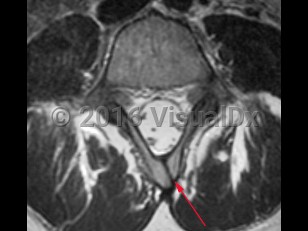

NTDs are classified as open (neural tissue exposed; anencephaly, myelomeningocele, meningocele) or closed (skin covering the defect; spina bifida occulta). Spina bifida occulta, also known as closed spinal dysraphism, is the least severe of the NTDs and results from the incomplete fusion of the posterior vertebral bodies, typically in the lumbosacral spine. Here we will focus on spina bifida occulta.

Spina bifida occulta may be suspected due to the presence of cutaneous lesions such as a dermal sinus tract, sacral dimple, hypertrichosis, hemangiomas, or a subcutaneous lipoma. Cases of spina bifida occulta can present at any age, and the severity of symptoms varies from asymptomatic to severe neurologic impairment due to tethered cord syndrome, secondary to abnormal tension on the spinal cord. Signs and symptoms of tethered cord syndrome secondary to spina bifida occulta include gait changes, bowel / bladder dysfunction, leg and back pain, and orthopedic deformities.